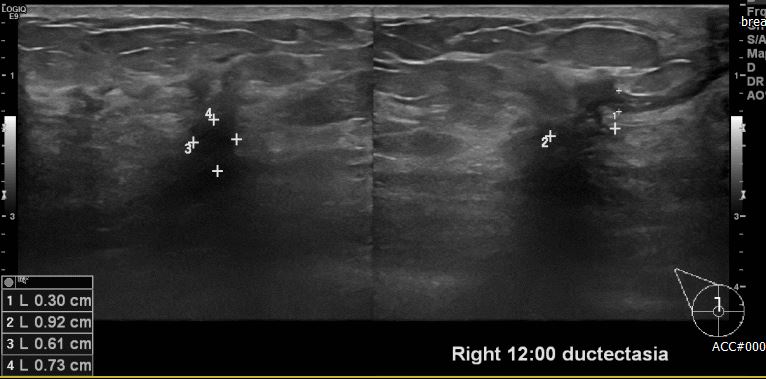

상기환자 건강검진상 이상 소견으로 내원 하신 60대 여성분으로 본원 초음파상 우측 12시 방향 유두 밑 부분 의심스러운 멍울 조직검사 시행하여 우측 침윤성 유관암 진단 되었습니다.